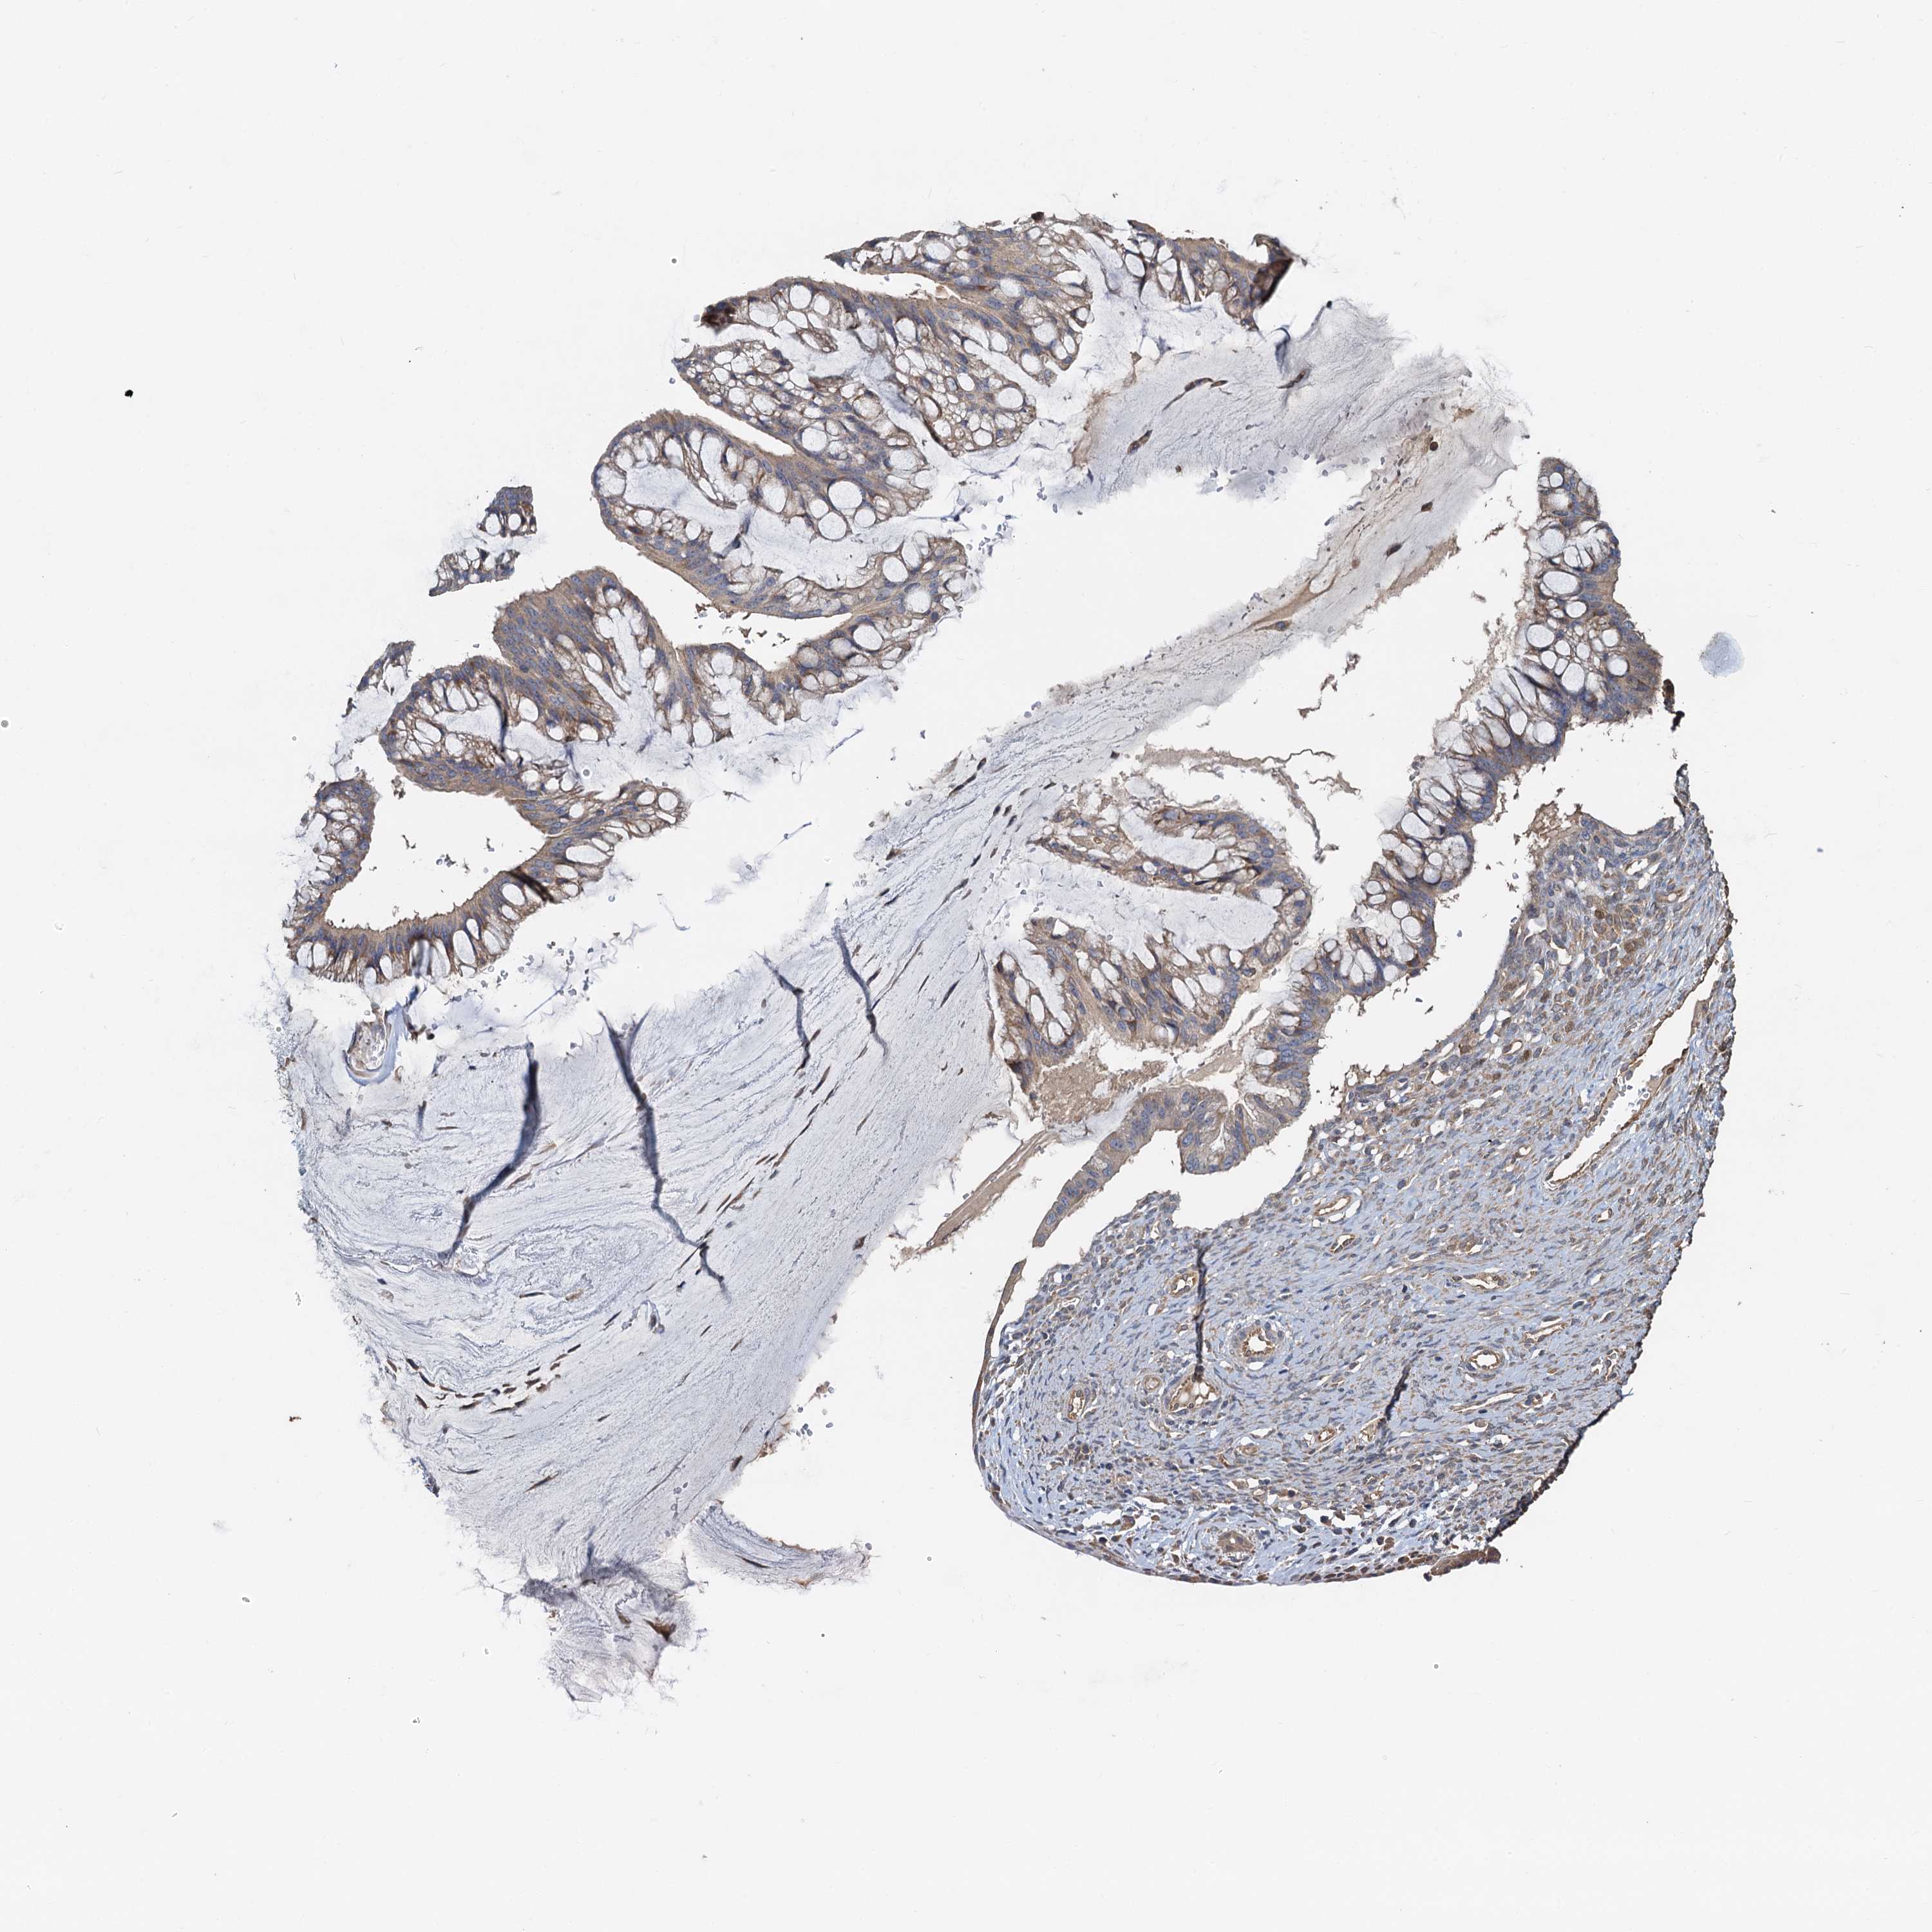

OVARIAN CANCER - Protein expressioni

A mouse-over function shows sample information and annotation data. Click on an image to view it in a full screen mode. Samples can be filtered based on level of antibody staining by selecting one or several of the following categories: high, medium, low and not detected. The assay and annotation is described here.

Note that samples used for immunohistochemistry by the Human Protein Atlas do not correspond to samples in the TCGA dataset.

Antibody stainingi

Antibody staining in the annotated cell types in the current human tissue is reported as not detected, low, medium, or high, based on conventional immunohistochemistry profiling in selected tissues. This score is based on the combination of the staining intensity and fraction of stained cells.

Each image is clickable and will lead to virtual microscopy that enables deeper exploration of all samples and also displays staining intensity scores, fraction scores and subcellular localization as well as patient and tissue information for each sample.

Antibody HPA040092

Staining

High

Medium

Low

Not detected

Intensity

Strong

Moderate

Weak

Negative

Quantity

>75%

75%-25%

<25%

None

Location

Nuclear

Cytoplasmic/membranous

Cytoplasmic/membranous,nuclear

Cystadenocarcinoma, serous, NOS

Carcinoma, endometroid

Cystadenocarcinoma, mucinous, NOS

Carcinoma, NOS